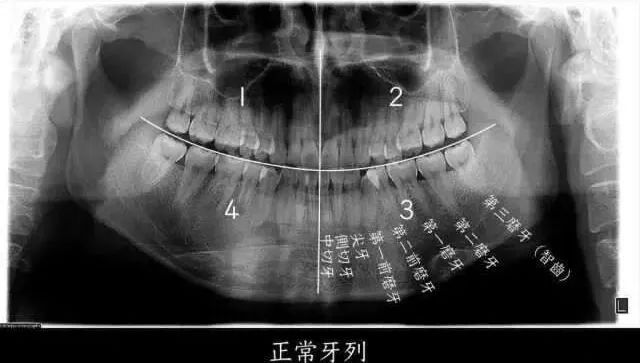

在医学上,智齿被称为第三磨牙,是从两个门牙的牙缝开始向内数的第八颗

乳侧切牙 乳犬牙 乳牙 第一乳磨牙 第二乳磨牙 恒牙 第三磨牙 第二